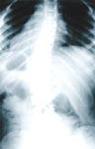

Методы лучевой диагностики. Основным методом

лучевой оценки сколиозов является обзорная рентгенография позвоночника в двух

проекциях (спондилография), которую проводят в положении лежа. Переднезаднюю

рентгенограмму выполняют с максимальным захватом всего позвоночника и крыльев

подвздошных костей. Метод позволяет: а) ориентировочно оценить состояние

позвоночника и выявить его анатомические особенности, прежде всего - пороки

развития; б) рассчитать величину деформации во фронтальной и сагиттальной

плоскостях; в) ориентировочно оценить торсию позвонков; г) определить степень

зрелости скелета по тесту Риссера (степень оссификации апофизов крыльев

подвздошных костей) и состоянию апофизов тел позвонков; д) оценить размеры

позвоночного канала. При необходимости переднезаднюю спондилографию дополняют

функциональными рентгенограммами при максимальных боковых наклонах. Функциональные

рентгенограммы в боковой проекции с разгибанием позвоночника проводят в том

случае, если деформация имеет комбинированный кифосколиотический характер.